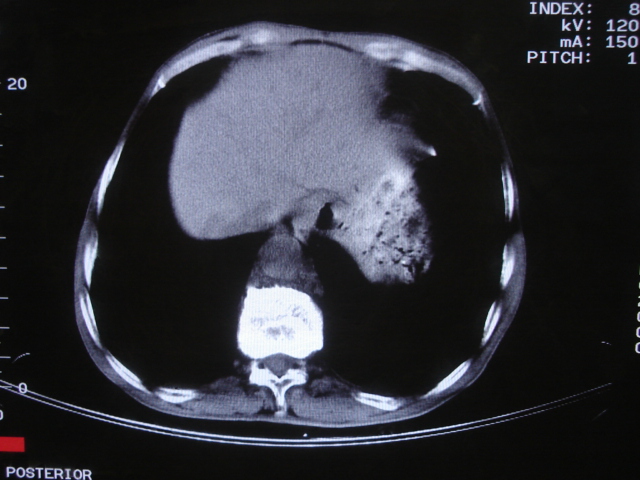

以下是引用深泽交通医院在2008-7-17 12:39:00的发言:[br]胃下垂;胃窦占位